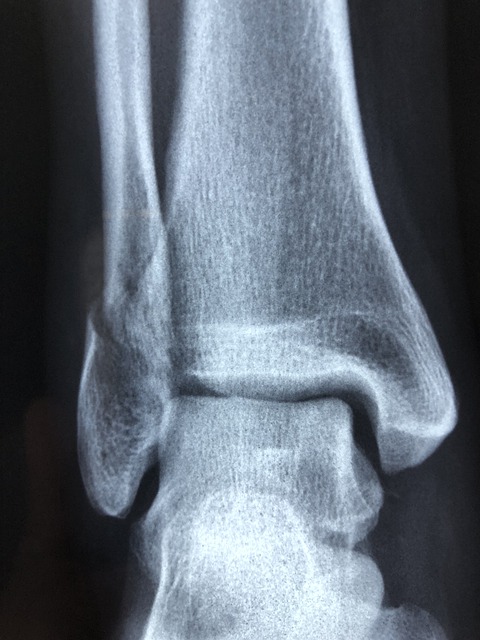

5. 발목 골절

발에 금이가 거나 골절된 경우 통증을 유발할 수 있습니다. 운동을 하거나 걷다가 발을 잘못 접질릴 때 발목 인대가 늘어나거나 뼈에 이상이 생겨 통증을 유발하게 됩니다. 발목에서 시작된 통증이 발뒤꿈치까지 이어질 수 있습니다. 발목이 골절된 경우에는 서있기도 힘들고 손으로 누를 때에 심한 통증을 유발하게 됩니다.

6. 발목 인대 손상

발목에 있는 인대가 늘어나거나 손상되는 경우에 발뒤꿈치에 통증이 생길 수 있습니다. 발목 인대는 생각보다 연약하여 발을 잘못 접질리거나 계단을 오르내리락 등산을 할 때 또는 점프 후 착지를 잘못했을 때 손상될 수 있습니다. 인대가 손상된 경우에는 발목에 지속적인 통증을 유발하게 되며 발목에 깁스를 차는 것으로 보전적 치료를 하게 됩니다.